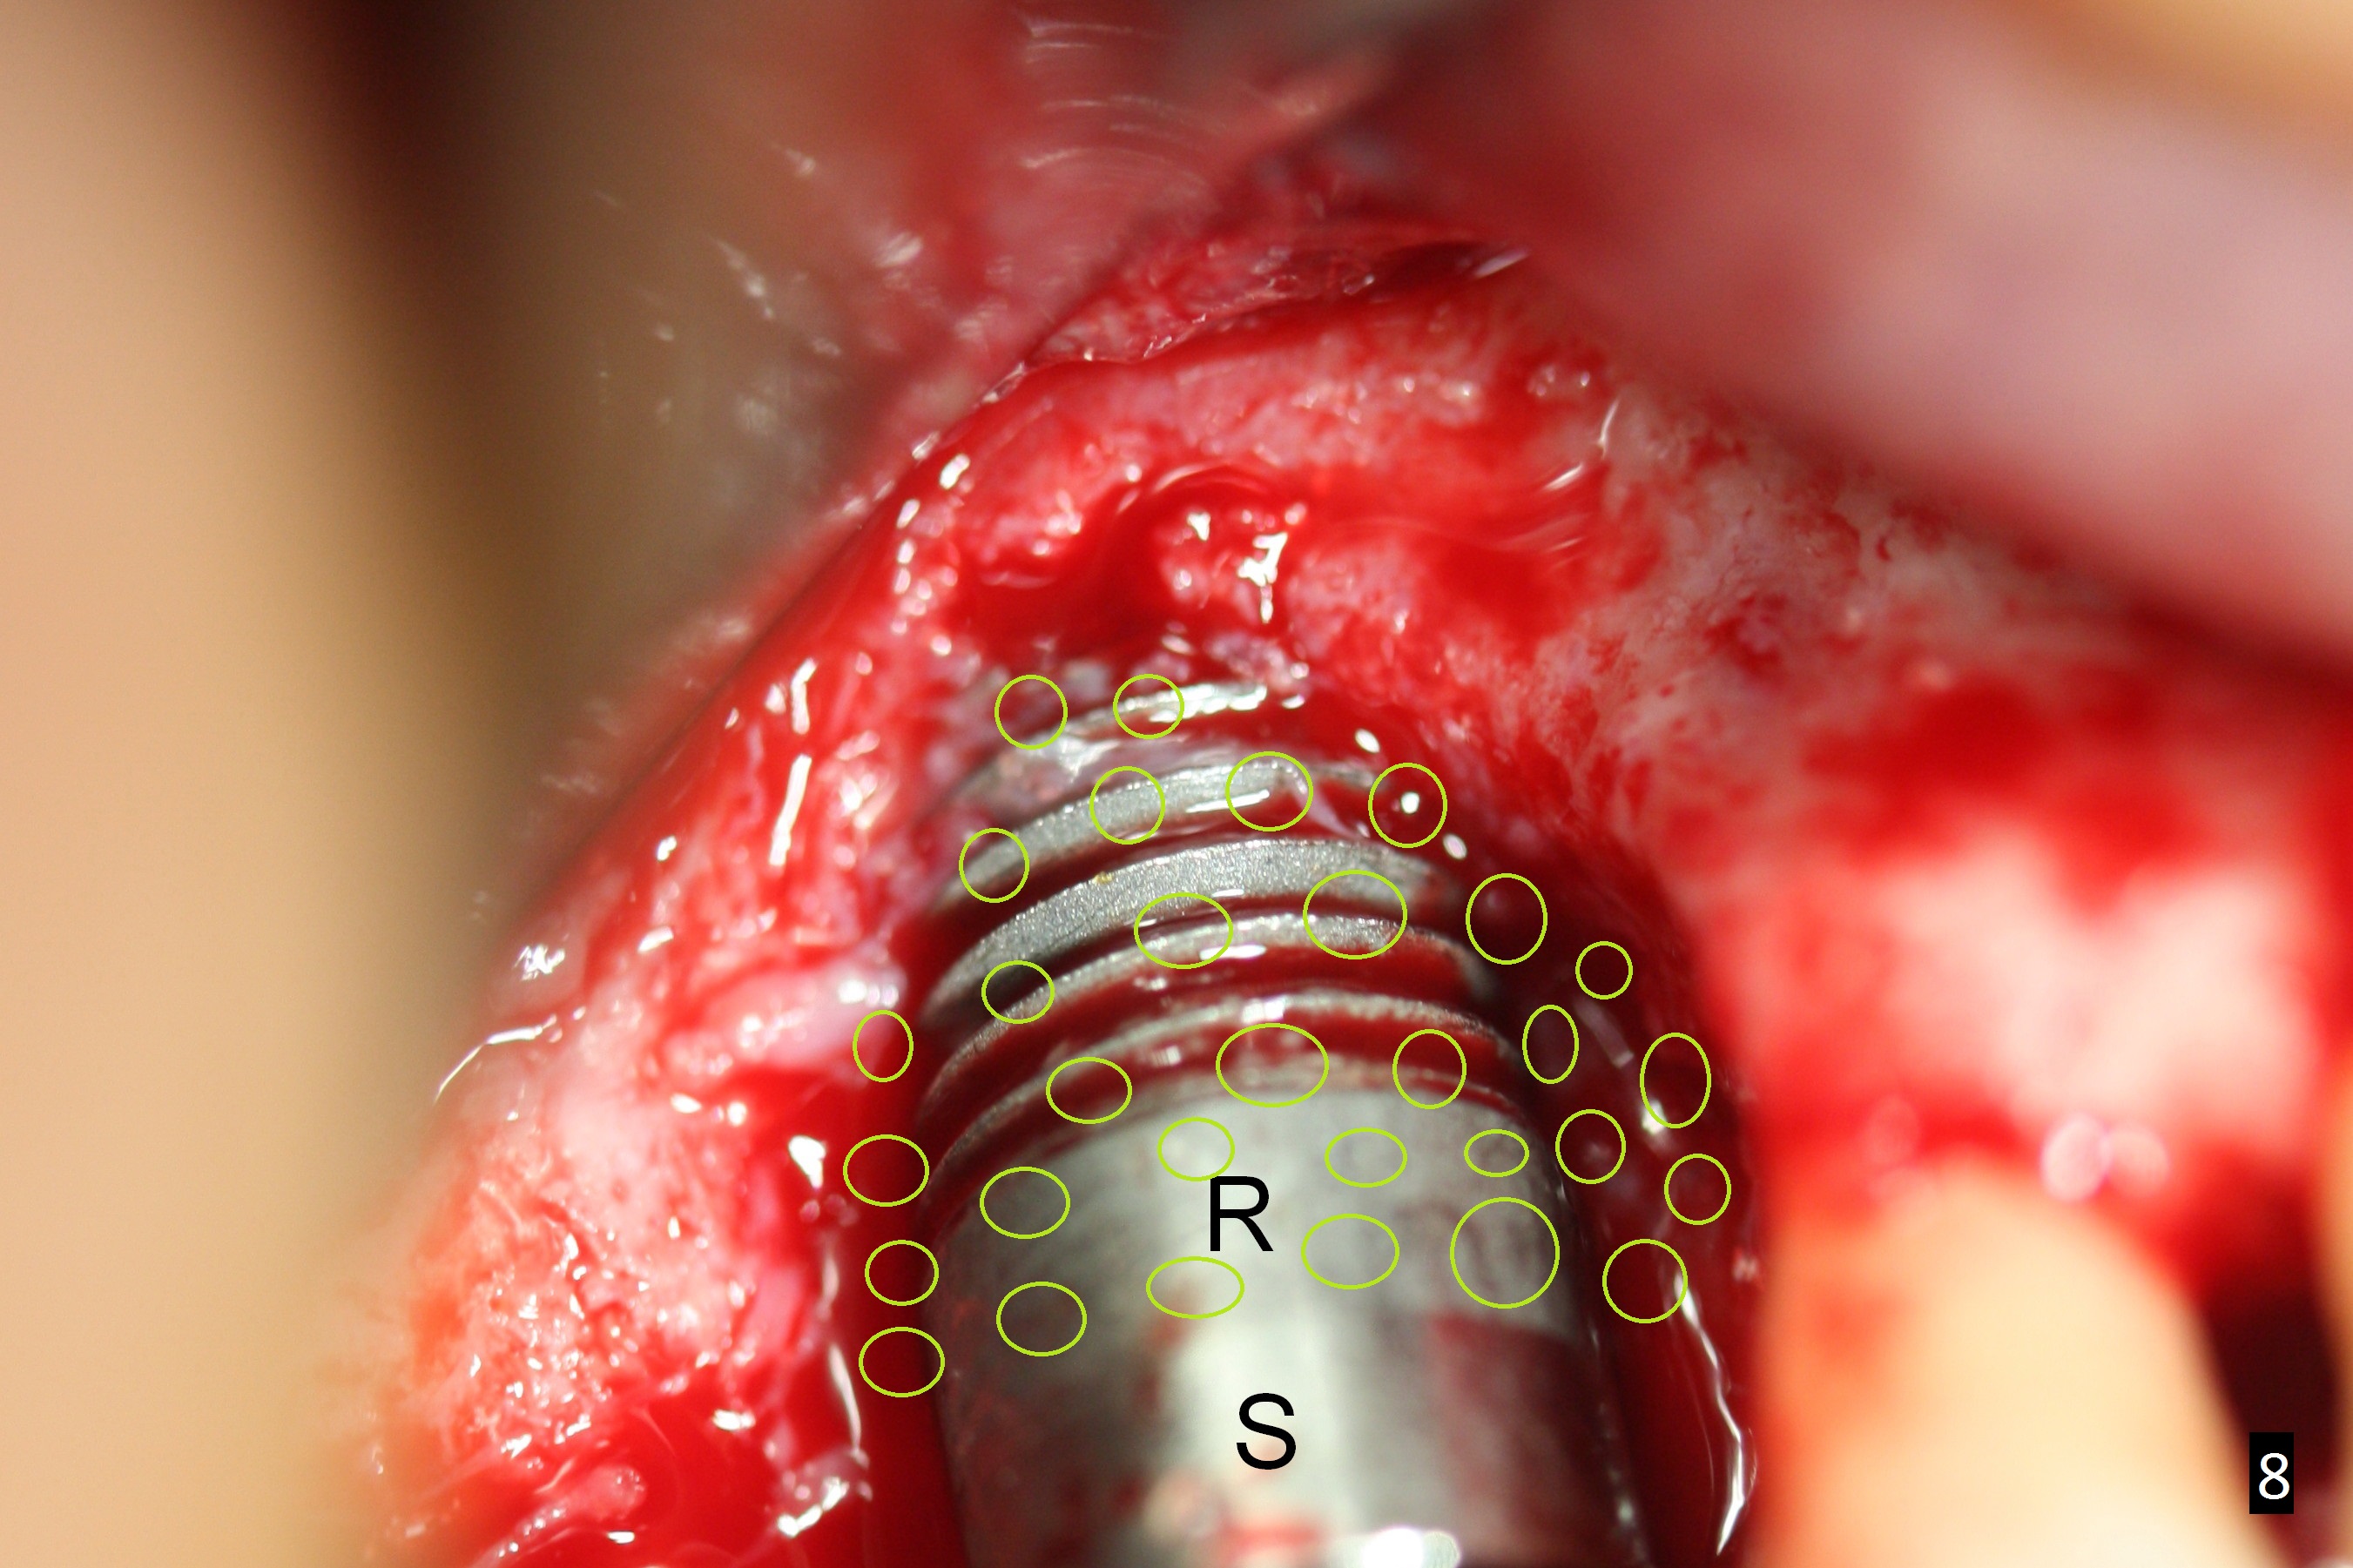

To prevent thread exposure complication, the implant should have at least 1-2 mm buccal clearance (gap (Fig.7 double arrows)). Place a relatively smaller implant (~6 mm) as palatal as possible. Pack bone graft in the remaining gap solidly (covering implant threads buccally and interproximally, Fig.8 (green circles)).